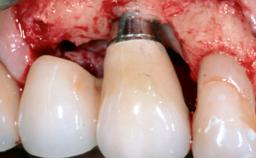

Treatment of Peri-Implant Mucositis at a Zirconia Implant